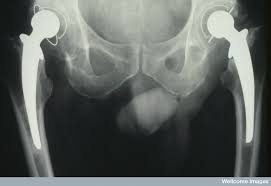

고관절 통증은 “허리 아픈가?” “무릎 아픈가?” 헷갈리게 시작하는 경우가 많습니다. 실제로 고관절은 통증이 사타구니(서혜부), 엉덩이, 허벅지 옆, 심지어 무릎까지 번져 느껴지기도 하거든요. 그래서 “증상 모양”을 먼저 정리해두면, 불필요한 걱정은 줄이고 필요한 진료는 빠르게 잡을 수 있습니다. 오늘은 고관절 통증 증상을 아주아주아주 쉽게 풀어드릴게요.

• 사타구니가 깊게 아픔 : “관절 안쪽” 느낌이 강하면 고관절 자체 문제(관절염, 충돌증후군, labrum 등) 가능성을 생각합니다.